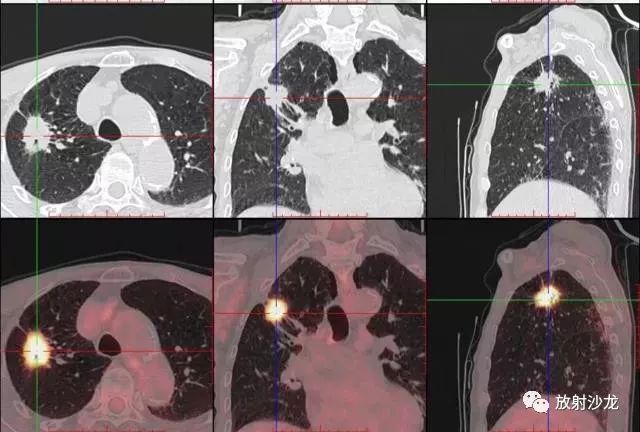

PET-CT等于PET+CT,包含PET(功能分子影像)與CT(解剖影像)的最優(yōu)化組合;即同時具有PET和CT的功能,但它絕不是二者功能的簡單疊加,因為PET與CT優(yōu)勢互補,“1+1>2”。PET-CT除了具備PET和CT各自的功能外,其獨有的融合圖像,將PET圖像與CT圖像融合, 可以同時反映病灶的代謝,可以早期診斷疾病的同時,明顯提高診斷的準確性。